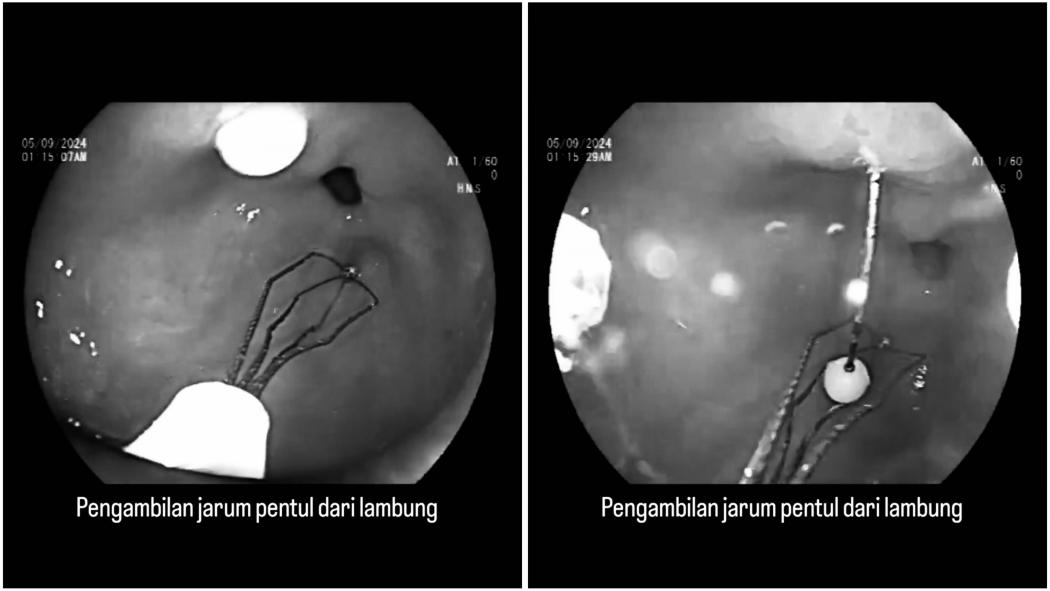

Tindakan endoskopi dipilih Dokter Ari Fahrial Syam untuk mengambil jarum pentul yang tertancap di lambung. (Foto: X)

JAKARTA, iNews.id - Viral di media sosial video proses pengambilan jarum pentul di dalam lambung yang dilakukan Dokter. Teknik pengambilannya menggunakan endoskopi.

Tindakan pengambilan jarum pentul yang tertelan dan menancap di lambung ini dilakukan oleh Ahli Penyakit Dalam Dokter Ari Fahrial Syam. Dia membagikan video medisnya di X dan viral.

Dokter Ari menjelaskan sebelumnya kalau jarum pentul bisa sampai tertancap di lambung gegara kebiasaan banyak perempuan berhijab yang suka gigit jarum pentul saat hendak mengenakan hijab.